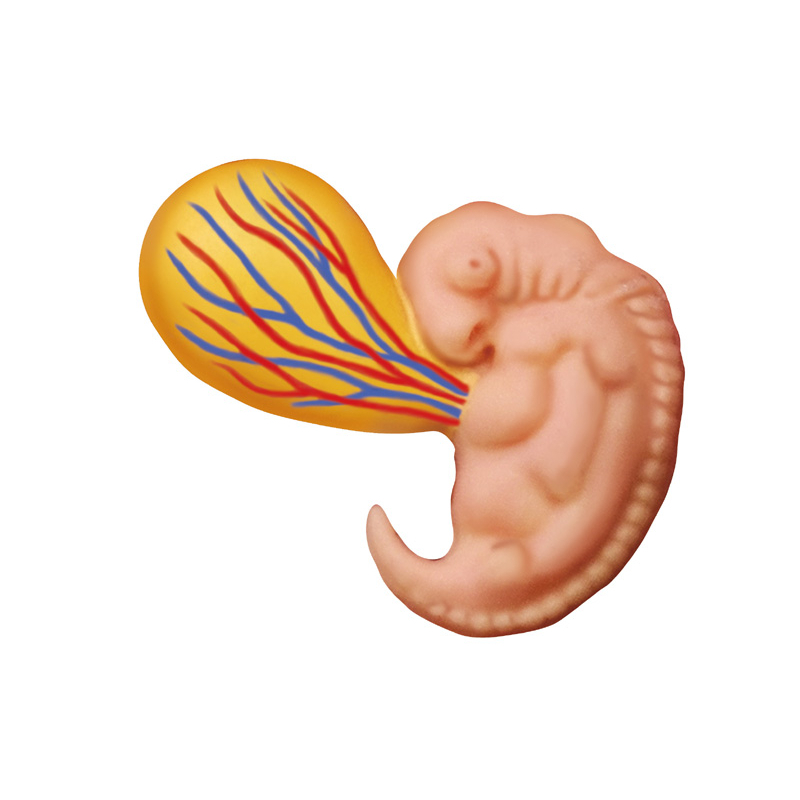

4D MASTER Human Anatomy Premium Embryo Development, Fertilisation to Fetus Development